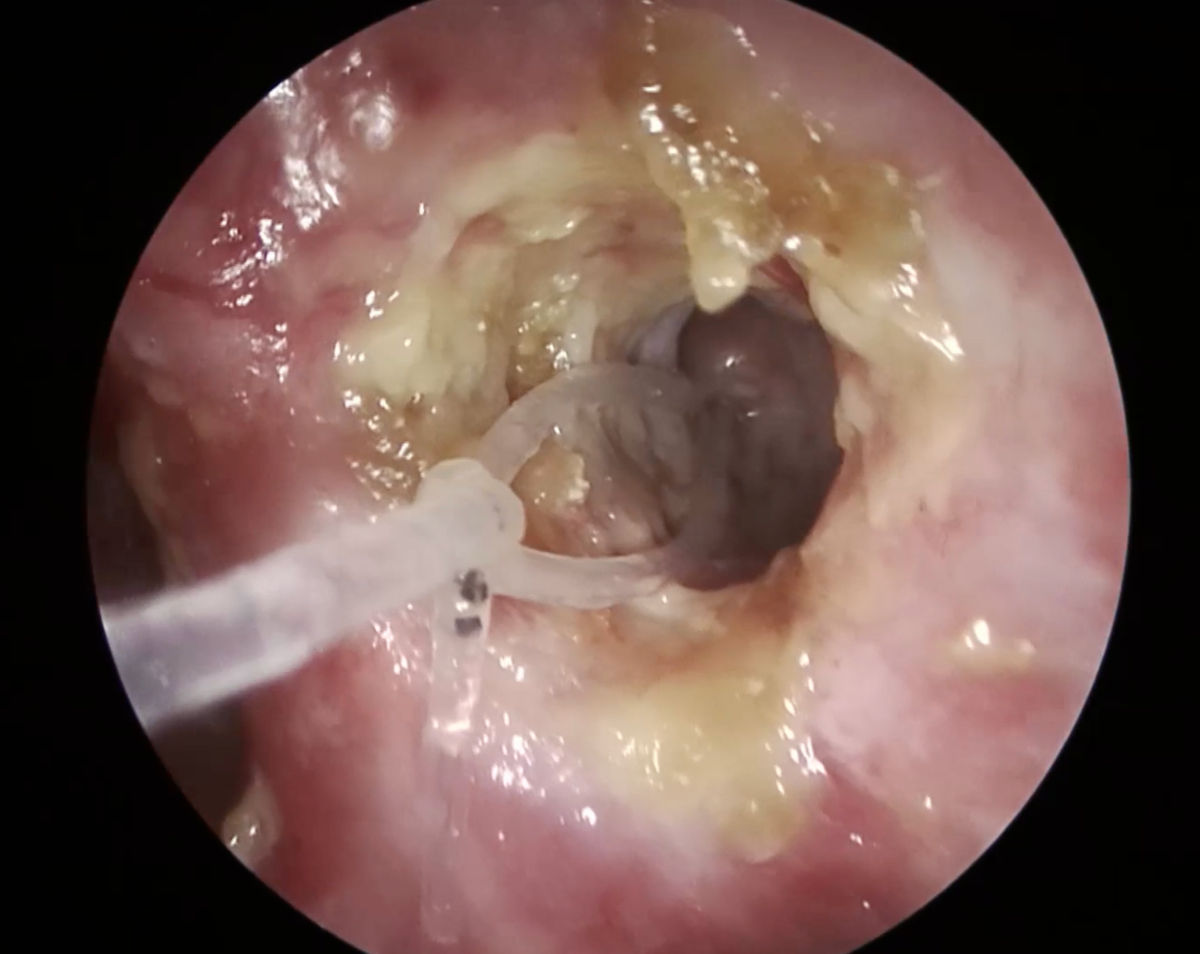

A 4 mm coronary balloon catheter (Boston Scientific, USA) was used to conduct a balloon dacryoplasty on the patient's left side (Fig. 10). An incision was made in the scar tissue developed after the previous DCR surgery (Fig. 11). The balloon catheter was introduced into the nasal cavity through the lacrimal canaliculus, lacrimal sac and the incised scar tissue. The catheter was inflated to 8 atm for 90 seconds, then it was deflated and removed (Fig. 12-13). After debriding the neo-ostium's periphery scar tissues, Mitomycin-C was applied. A significant internal common opening was visible in the immediate postoperative period. The ostium was big, anatomically correct, and functionally patent at the 3-month follow-up. At six months of follow-up, the patient was symptom-free and still receiving immunosuppressive treatment (Fig. 14-15).

Figure 14. Endoscopy view of the left nasal cavity: ostium at 1 month after surgery (note the silicone stent inside the ostium).